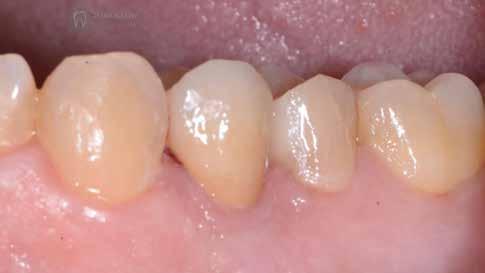

A 26 éves férfi páciens azzal a kéréssel kereste fel a rendelőnket, hogy a frontfogai esztétikusabb megjelenését szeretné elérni. A páciens jó általános egészségi állapottal rendelkezett, nem szenvedett allergiáktól és nem kellett rendszeresen gyógyszereket szednie. A páciens lehetőség szerint kerülte a fogai megmutatását. Rendkívül zavarónak találta a nagymetszői között, a középvonalnak megfelelően látható rést, a fogain látható kopási jeleket, valamint a fogai méretét is túl kicsinek találta. A szájüregi vizsgálat során megállapítottuk, hogy a nagymetsző fogai (11, 21) élharapásban vannak, valamint az alsó fogíven kismértékű torlódást észleltünk. A felső frontfogakon

(13-23) attrícióra utaló jeleket találtunk. A fogak kopása a nagymetszőfogaknak megfelelően volt a legkifejezettebb (1. ábra) . Az előbbiekben említett fogak (11, 21) ezen kívül némileg elfordultak, és jelentősebb méretű diasztéma volt köztük. A páciens Angle I.-osztályú állcsontrelációs helyzettel rendelkezett. A vizsgálat során feltűnt, hogy a páciens csak nagyon óvatosan mert mosolyogni (2. ábra)

A szájüregi vizsgálat során nem találtunk szuvas léziók jelenlétére utaló eltéréseket. A nagymetszőfogakon megfigyelhető jelentős mértékű kopás ellenére nem észleltünk craniomandibuláris diszfunkció jelenlétére utaló jeleket. A vizsgálat befejezését követően a pácienst tájékoztattuk a különböző kezelési lehetőségekről. Az esztétikai megjelenés javítása érdekében először egy alignerekkel végzett fogszabályzó kezelés elvégzését, majd a harapási helyzet optimalizálását követően a felső frontfogai kompozittal történő direkt felépítését vagy héjakkal történő ellátását (pl.: non-prep héjak) javasoltuk (3. és 4. ábra).

A fogazat minimálinvazív módon készített héjakkal történő ellátásához a fogaknak olyan pozícióban kell lenniük, amely lehetővé teszi az esztétikai megjelenés additív eljárások alkalmazása mellett történő optimalizálását.1. ábra: Kiindulási állapot. A felső nagymetszőfogak élharapásban vannak. 2. ábra: Az orthodonciai kezelés megkezdése előtt készített intraorális felvétel. A páciens csak óvatosan mer mosolyogni. 3. és 4. ábra: Digitálisan megtervezett kezelés.

A kezelések második fázisában a pácienssel közösen non-prep/ minimálinvazív héjak készítése mellett döntöttünk (6. és 7. ábra).

Az ilyen jellegű ellátás során csupán a lehető legkisebb mennyiségű foganyag kerül eltávolításra. A minimálinvazív beavatkozás elvégzését lehetővé tevő feltételeket a fogszabályzó kezelés során alakítottuk ki. A fogazat minimálinvazív módon készített héjakkal történő ellátásához a fogaknak olyan pozícióban kell lenniük, amely lehetővé teszi az esztétikai megjelenés additív eljárások alkalmazása mellett történő optimalizálását. Azonban az ellátás során előbbiekben felsoroltakon kívül más szempontokat is figyelembe kell vennünk. Amennyiben a páciens a jelenleg látható fogszínéhez képest jelentős változást szeretne elérni, úgy sokkal vastagabb héjak készítésére van szükség, és az ezáltal megnövekedett helyigény miatt sok esetben nincs lehetőség kizárólag additív eljárások alkalmazására (8. ábra). Mivel a cikkben bemutatásra kerülő eset ellátása során a fogazat helyzeti rendellenességei az előzetes orthodonciai kezelés keretei között korrekcióra kerültek, ezért lehetőségünk adódott a restauratív fázis minimálinvazív módon történő elvégzésére. Az általunk alkalmazott terápia hátrányai között szerepelt, hogy az elvégzett beavatkozások időigénye miatt a tervezett végeredményt csupán viszonylag hosszú idő után tudtuk elérni.

A páciens teljesen elégedett volt a kezelések befejezését követően elért esztétikai végeredménnyel (9. ábra). A terápiás erőfeszítéseink eredményeinek köszönhetően újra képes felszabadultan nevetni és mosolyogni. A cikkben bemutatásra kerülő eset jól példázza a multidiszciplináris beavatkozások alkalmazásában rejlő előnyöket. A megfelelő sorrendben végzett orthodonciai és restauratív kezelésekkel lehetővé vált a páciens mosolyának minimálinvazív módszerekkel történő optimalizálása. A körültekintő tervezésnek köszönhetően nem került sor felesleges beavatkozások elvégzésére, és emiatt a kezelések befejezéséhez szükséges idő sem nyúlt a szükségesnél hosszabbra. Arra is felhívnánk a figyelmet, hogy a jól megszervezett, továbbá a lehető legkevesebb rendelési időt felhasználó kezelések – a beavatkozásokat végző fogorvosok számára is – rendkívül kedvezőek lehetnek.